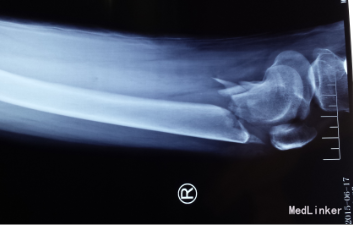

患者,女性,36岁,发生车祸,膝关节疼痛,活动受限两小时,入院检查治疗。无既往病史。

左膝部肿胀,压痛明显,叩击痛(+),左膝关节活动障碍,左膝前有伤口。严重的软组织损伤。进行常规检查,无高血压,心脏病。

光片诊断患者骨折端粉碎,软组织损伤,发生股骨踝间骨折。采用切开复位,普通钢板、髁部支撑钢板内固定治疗股骨髁间粉碎性骨折。